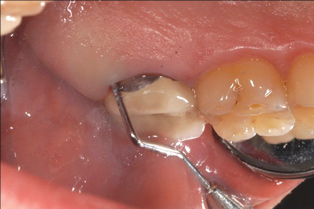

Fig 3. Tooth No. 28 had a Class V filling that failed with recurrent decay (Fig 3). A tuberosity CTG with a 1.5 mm thickness was placed, and after 1 year there was no keloid-like appearance (Fig 4).

Figure 3

Fig 4. Tooth No. 28 had a Class V filling that failed with recurrent decay (Fig 3). A tuberosity CTG with a 1.5 mm thickness was placed, and after 1 year there was no keloid-like appearance (Fig 4).

Figure 4

Class V fillings are artificial materials that tend to fail at the apical extent and have poor long-term success (Figure 3).1 Conversely, CTGs are natural and attach to the root surface and have high long-term success (Figure 4).1

Regarding the avoidance of a gingivoplasty procedure later, there appears to be nothing in the literature describing the ideal thickness of a tuberosity CTG. From palatal and allograft thickness recommendations, one could hypothesize that the thickness be between 0.75 mm and 2 mm. This article will propose a graft thickness between 1 mm to 1.5 mm (Figure 3 and Figure 4) for the optimal functional and esthetic outcome and will discuss various procurement and fileting techniques.

Dense CT presumably is less susceptible to shrinkage than less-dense CT. One problem with denser CT may be the need for a longer amount of time to blend in with adjacent non-grafted areas. Due to density, a CT graft might never completely blend in and always demonstrate an unesthetic keloid-like appearance. Therefore, with tuberosity tissue, adjusting the tissue thickness prior to placement of the graft is highly clinically relevant. This may be why periodontists have been reluctant to use tuberosity tissue as CT. Palatal tissue has less-dense CT than tuberosity tissue and, therefore, the authors hypothesize and have observed, shrinks more. Because palatal tissue has been the predominant tissue used in CTG, clinicians have become used to the shrinkage associated with the palatal CT and may not realize the need to thin a dense CTG to prevent a keloid-like appearance. Thus, in the past when a tuberosity was used for this purpose, if it was not properly trimmed it would have frequently resulted in an unesthetic keloid-like appearance. The tuberosity CTG should be trimmed to 1 mm to 1.5 mm thick to avoid the need for a future procedure to adjust tissue thickness for esthetics (Figure 3 and Figure 4, Figure 16 and Figure 17).